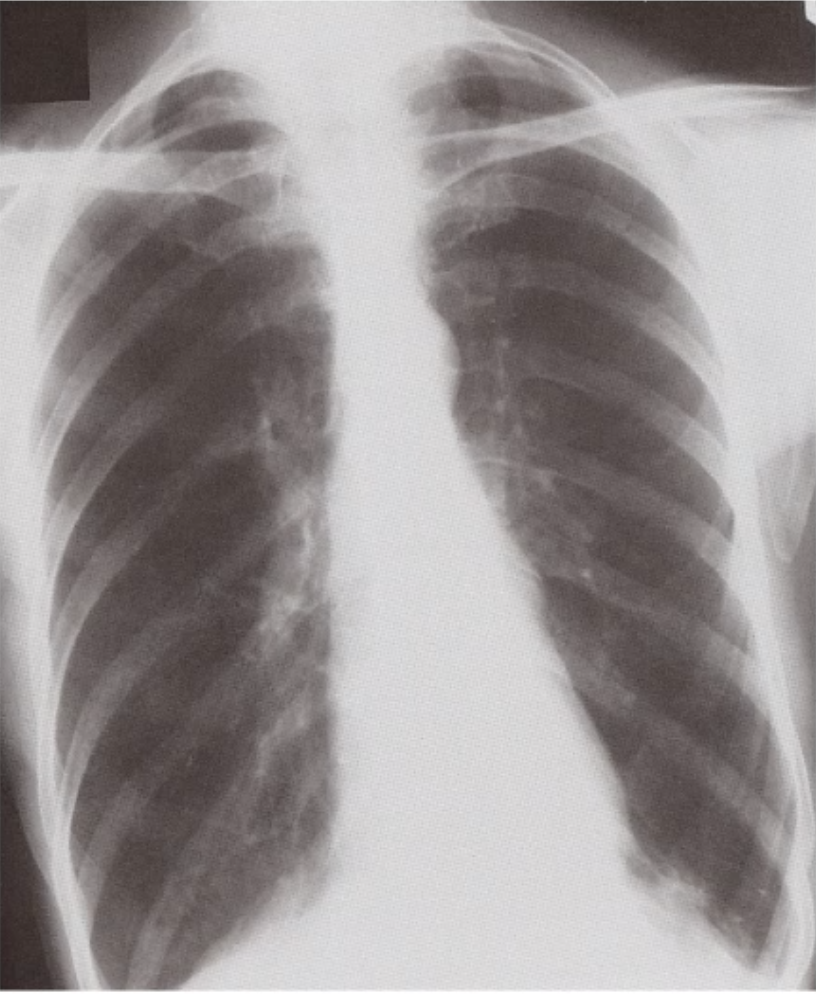

Which diagnosis is suggested by this CXR?

Pneumothorax

No lung markings on affected side

Mediastinum deviated away from the lesion